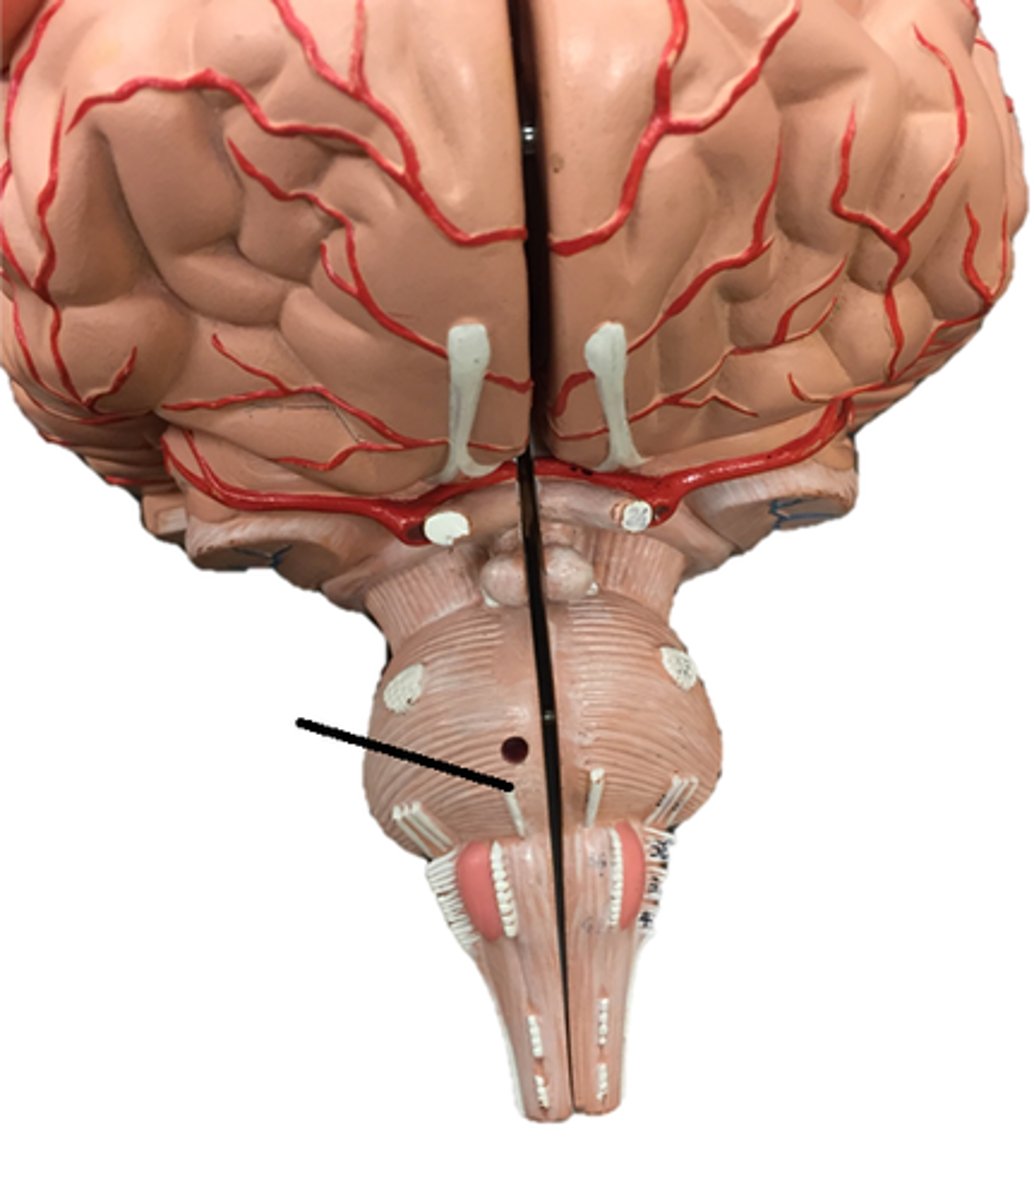

pons

medulla oblongata

olive